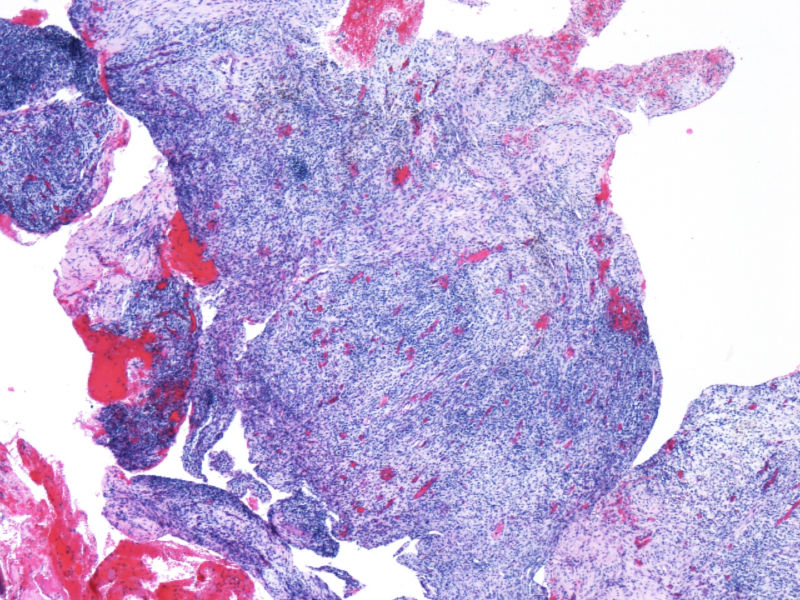

最终诊断为:ALK阳性的间变性大细胞淋巴瘤,淋巴组织细胞变异型。

拿出来的目的:本例始发于骨骼,临床提示脓肿或骨髓瘤,ALK阳性但EMA阴性,细胞毒只有一个标记阳性,本例CD4不阳性。因为CD30和CD15均有非肿瘤细胞阳性的情况,所以对于这个骨骼病例,细胞少而退变,因此最初没有信心诊断,但ALK一般不在非肿瘤细胞内阳性表达,所以最终还是诊断了ALCL。

此病例是非常特殊,其表现为:

1)ALCL很少原发于骨组织,

2)肿瘤细胞免疫表型特殊, CD30+CD15+ALK-1+CD43+Perforin+, 而其他PanB细胞和PanT细胞的标记均为阴性。

3)楼主诊断ALCL主要根据是 ALK-1+, 很有说服力!